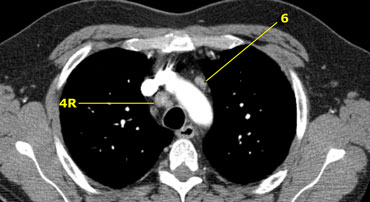

On the left we see 4R paratracheal nodes.

In addition there is an aortic node lateral to the aortic arch, i.e. station 6 node.

On the left an image just above the level of the pulmonary trunk demonstrating lower paratracheal nodes on the left and on the right.

In addition there are also station 3 and 5 nodes.